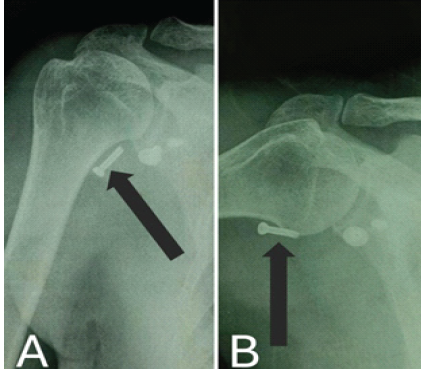

A 38-year-old male with a history of right shoulder instability in the past was managed with the Latarjet procedure 4 years ago. The patient had an uneventful post-surgical period, but symptoms recurred a year later without any significant event. He presented to us with complaints of right shoulder pain and instability since 3 years, having experienced multiple episodes of dislocations, which were managed with closed reduction at different centers. On examination, the Beighton score was five. 1 cm wasting was noted in the right arm. Sensations over the arm were intact. Tests for anterior instability, such as apprehension, relocation-release, and anterior drawer, were positive. There were no signs of instability in posterior and inferior directions. He had a nearly complete range of motion in all planes but was apprehensive to use the arm for overhead activities and lifting heavy objects. X-ray and computed tomography (CT) scan were done, which revealed a displaced as well as a broken screw near the right glenoid, likely from the previous surgery (Fig. 1 and 2). The anteroinferior part of the glenoid appeared to be resorbed. Bone loss was quantified using the perfect circle method in oblique sagittal plane, which was approximately 27% (Fig. 3). Infective etiology was ruled out via clinical examination and radiological investigations.

Figure 1: X-ray on presentation. (a) Anteroposterior X-ray in 10° abduction, (b) Anteroposterior X-ray in 60° abduction, both showing a displaced screw in soft-tissue marked with a black arrow.